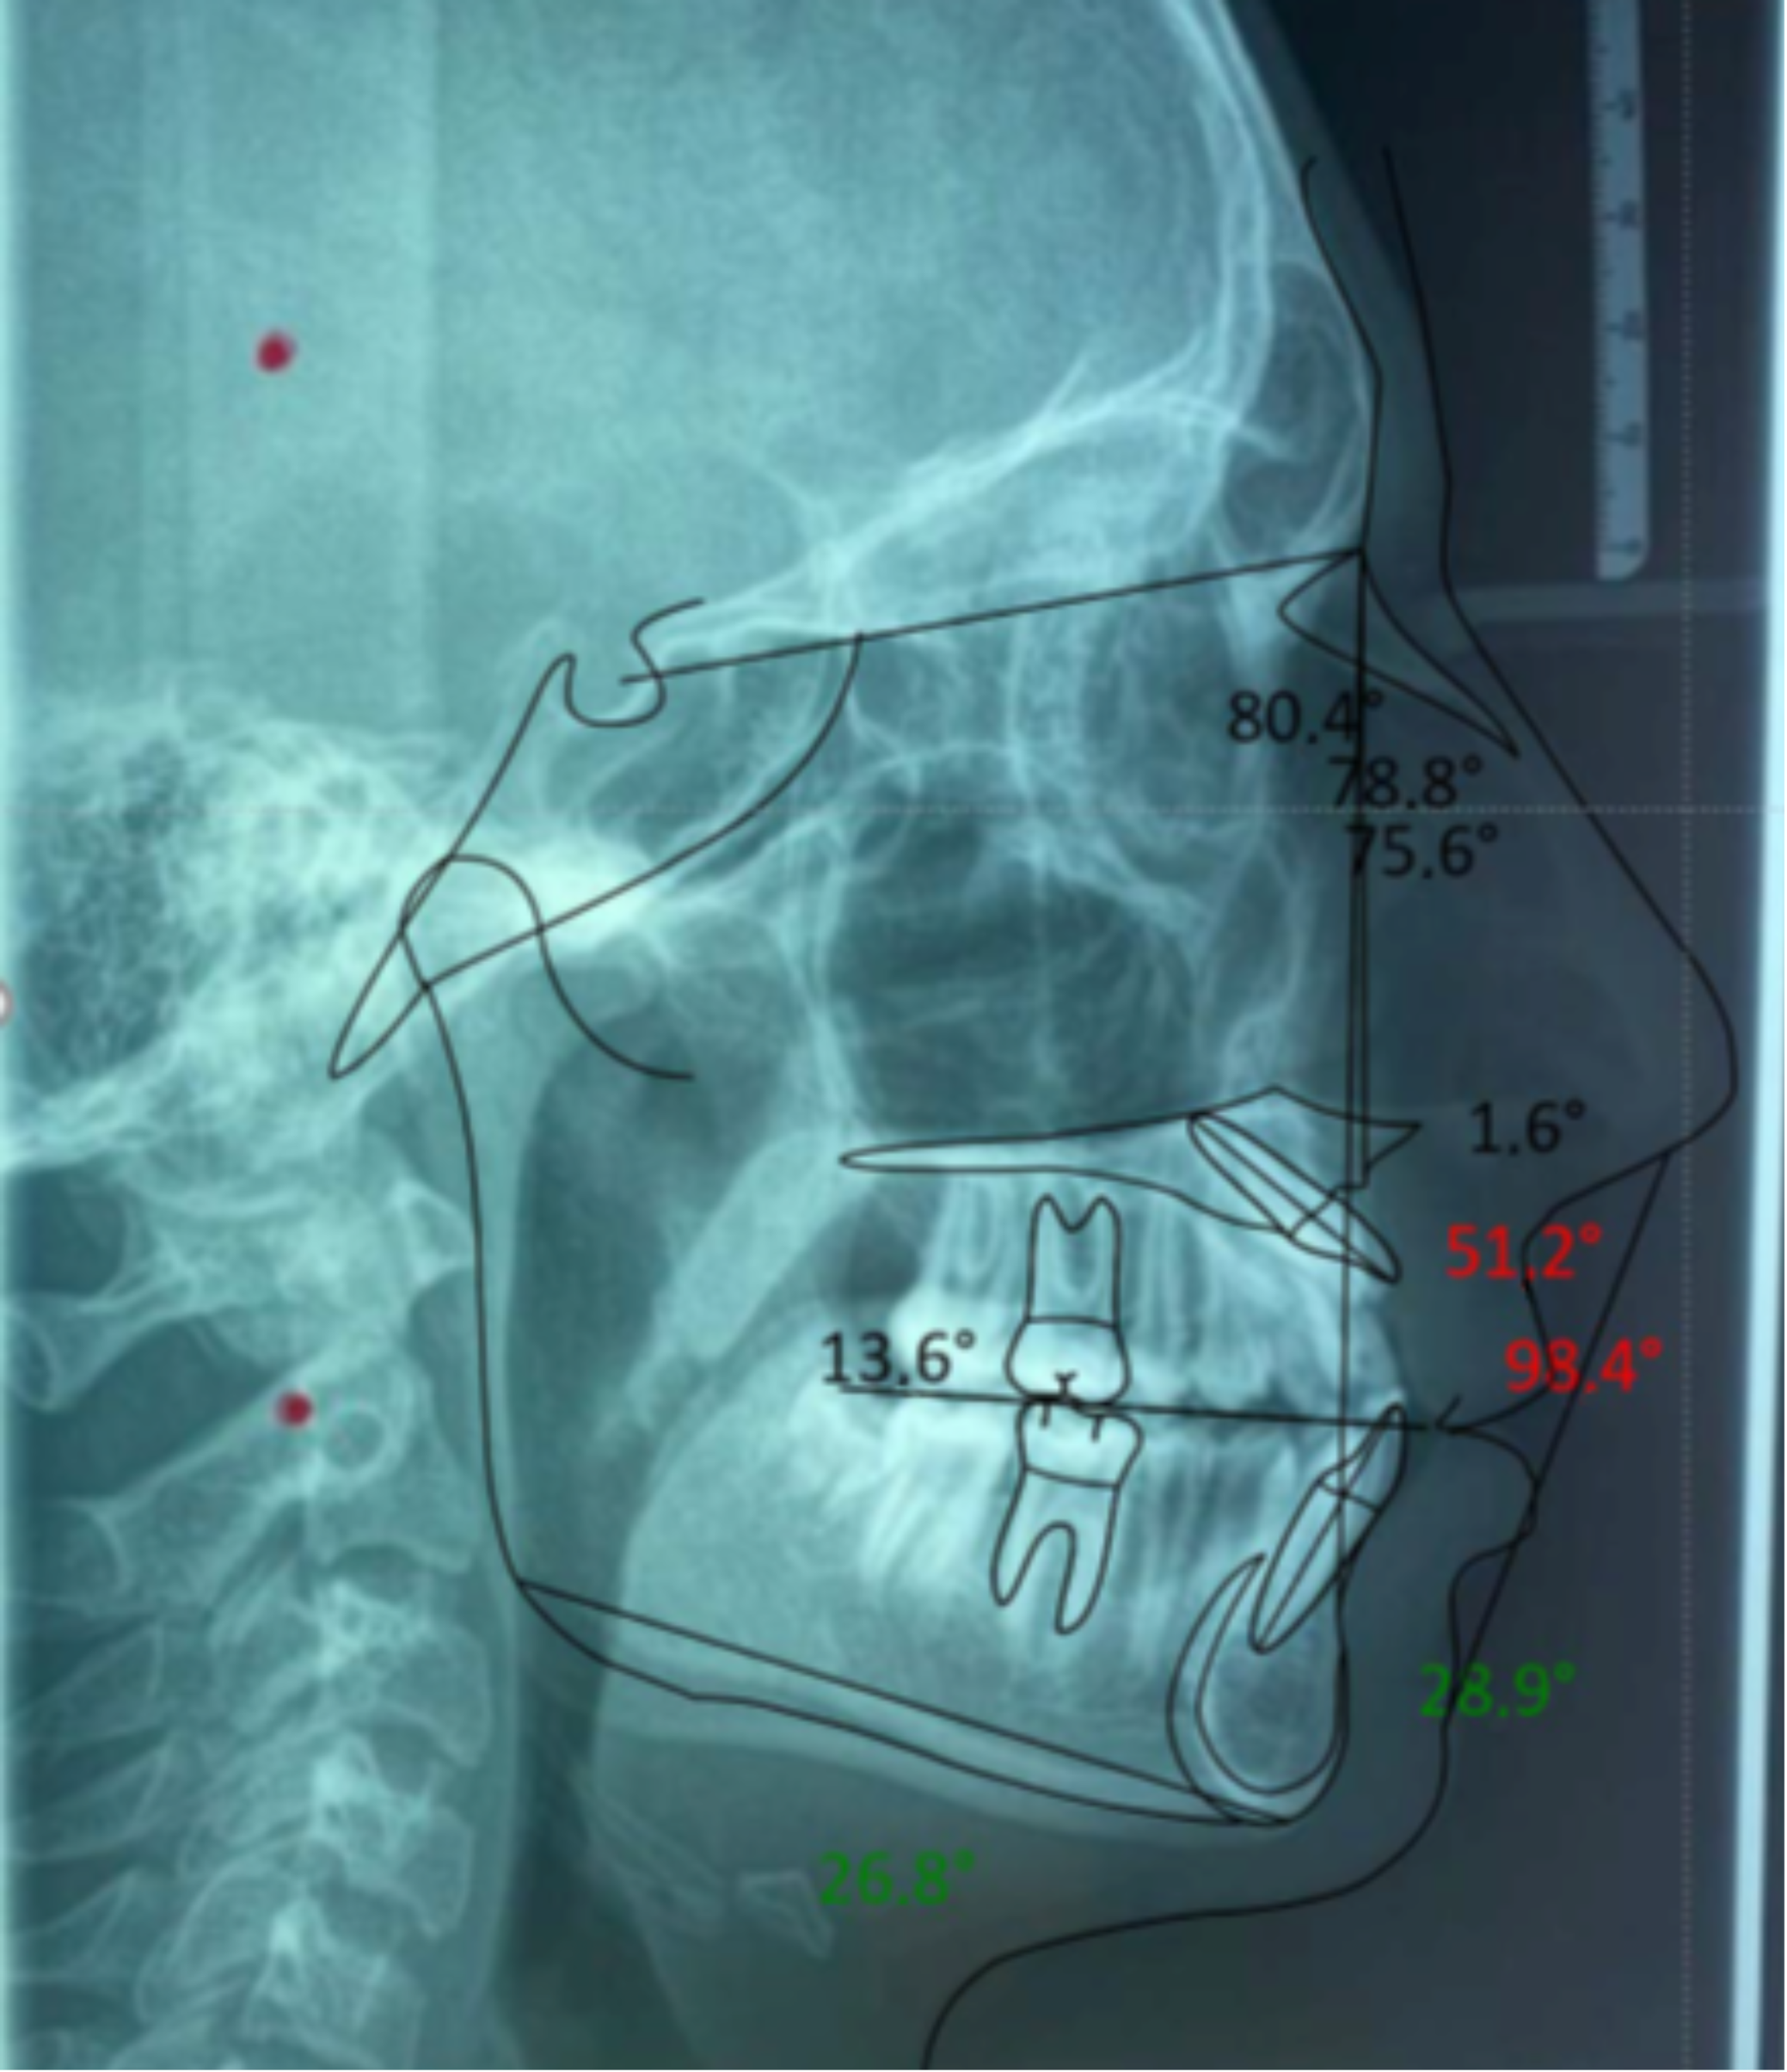

| Values | Normal | |

|---|---|---|

| SNA | 80.4° | 82°+/−2° |

| SNB | 78.8° | 80°+/−2° |

| ANB | 1.6° | 2°+/−2° |

| GONIAC ANGLE | 116.1° | 130°+/−7° |

| INTERINCISIVE ANGLE | 98.4° | 131°+/−6° |

| SUPERIOR INCISOR ANGLE | 51.2° | 22°+/−2° |

| INFERIOR INCISOR ANGLE | 28.9° | 25°+/−2° |